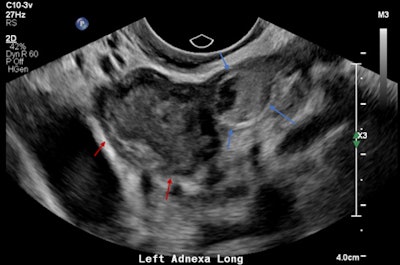

A 32-year-old female presented with severe constant left lower abdominal pain, per vaginal spotting and nausea. A pelvic ultrasound performed at six weeks' gestation demonstrated a viable intrauterine gestation and a small perigestational hematoma. A heterogeneous mass was noted abutting the left ovary. It featured peripheral vascularity, but no internal vascularity. There was small-volume pelvic free fluid with low-level internal echoes consistent with hemoperitoneum (see three images below).

Left adnexal heterogeneous mass with an echogenic tubal ring sign (blue arrows) adjacent to the left ovary (red arrows).